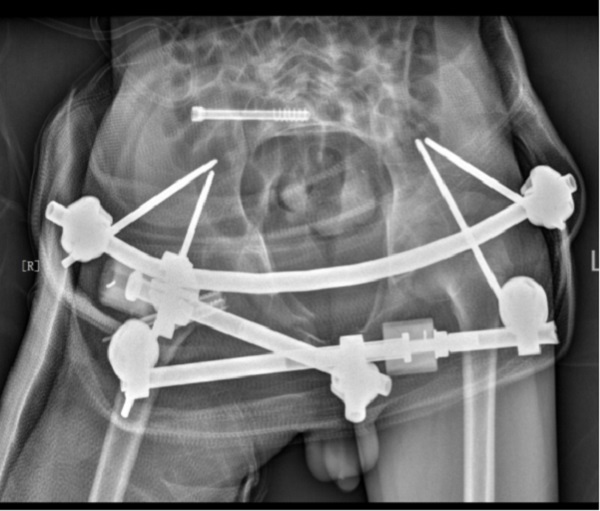

小陈骨盆骨折Tile分型为C1-2骶髂关节骨折并脱位;Torode-ieg儿童骨盆骨折分型为4b型,右侧骨盆整体移位,同时合并右侧股骨颈骨折,需手术复位固定。潘建宏主任考虑到患儿年龄小,手术难度大,科室多次讨论后,计划采取闭合复位微创固定,在全麻下进行了“骨盆骨折及右侧股骨颈骨折闭合复位内固定术”,闭合复位成功后,骨盆后环经皮空心螺钉固定、骨盆前环使用外固定固定,股骨颈骨折使用经皮空心钉及克什针固定,术后使用髋人字石膏固定制动,微创手术顺利完成,术后,患者恢复顺利,现已出院。

儿童骨盆骨折发病率低,需要手术治疗的严重骨盆骨折病例极少。由于手术难度大,儿童骨盆骨折多采用保守治疗,近年的回顾性研究认为保守治疗畸形愈合率较高,可能引起骨盆倾斜、下肢短缩,而手术解剖复位固定明显能获得更好的治疗效果。